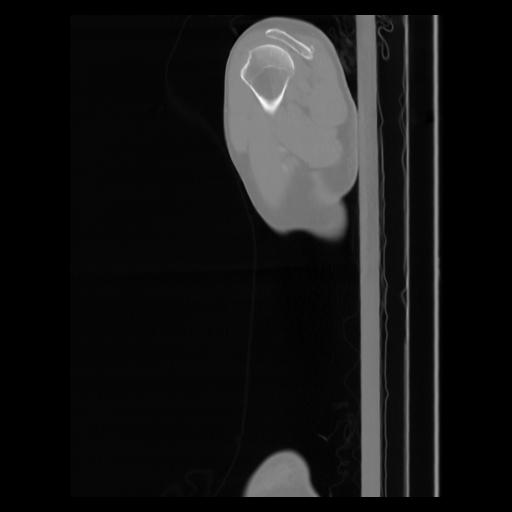

30 CUERPO,CE,Sagittal,3.000,CUERPO,Sagittal,